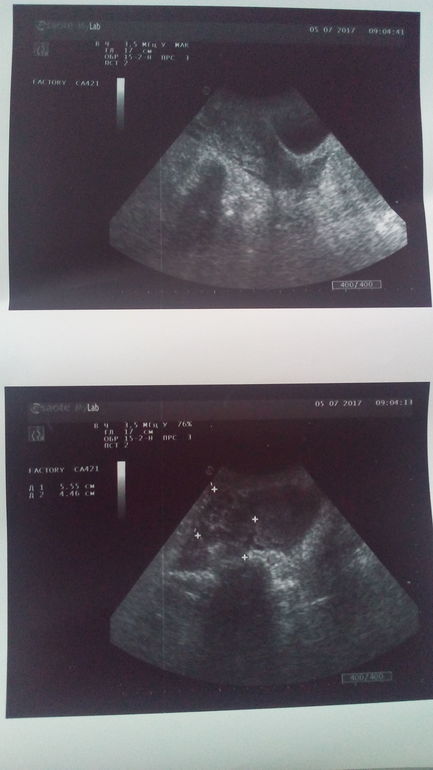

Так я была в больнице) мне прописали папаверин, дюфастон и фольку. На УЗИ ничего не увидели. Подозревают или воспаление, или внематочную. Выделения прекратились) ттт